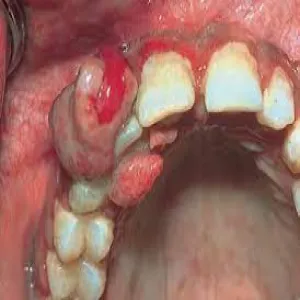

Nadziąślak

Nadziąślak, epulis